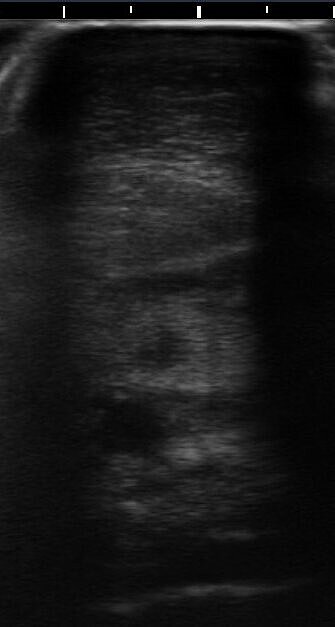

Trächtigkeitsuntersuchung